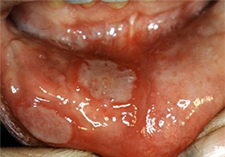

Aphthous Ulcers (a.k.a aphthous stomatitis, canker sores)

Presentation

Signs

Based on the clinical examination and on the patient’s medical history, a diagnosis of aphthous ulcers is determined.